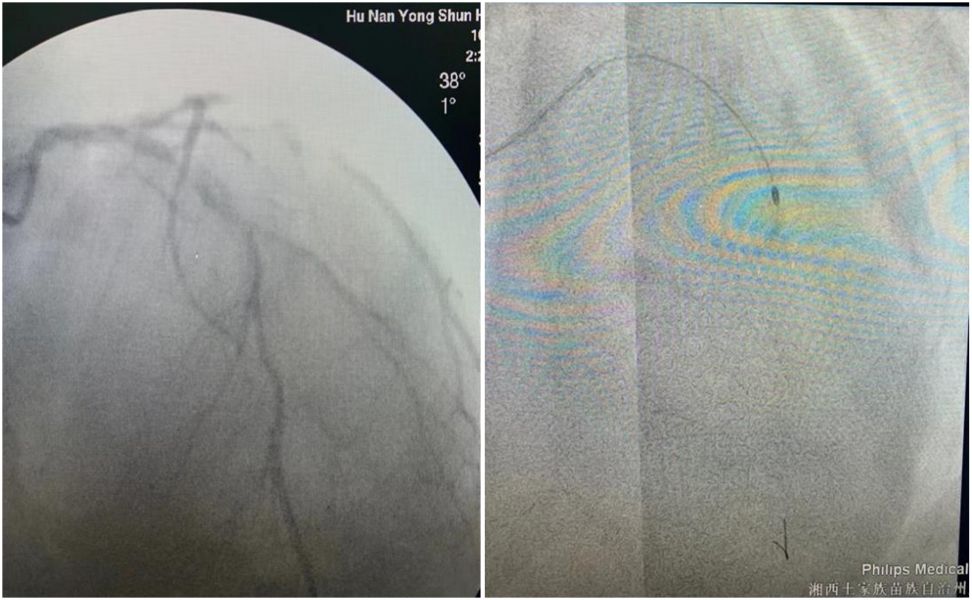

术前造影和旋磨术中